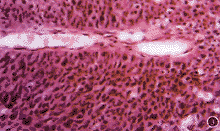

患者男,60岁。1993年8月因左眼溢泪,无脓,曾在当地医院以“慢性泪囊炎”行左泪道探通术,术后溢泪症状好转。半个月后,左泪囊部皮肤红、肿、疼痛,未扪及肿物,诊断为急性泪囊炎,予以抗生素治疗症状好转。以后曾反复发作2次,均以抗生素治疗。1996年10月24日,左泪囊区皮肤红、肿,硬结,局部压痛、无热,来我院就诊,仍按急性泪囊炎予以热敷,局部湿敷雷夫诺尔及0.25%氯霉素眼液滴眼。20天后,左泪囊区呈高度肿胀隆起,皮肤呈紫红色、表面光滑、质地较硬。泪囊X线平片示粘膜肥厚,未见骨壁破坏,按急性泪囊炎行泪囊切开术排脓,术中仅见极少量脓液(经培养无细菌生长),继续给予抗生素治疗。术后1周,左泪囊区皮肤可见约2.0 cm×2.0 cm×2.5 cm肿物,呈分叶状、质硬,表面皮肤破溃,中央似有波动感,左耳前淋巴结未扪及,继续口服抗生素。1996年11月29日行局部活检,病理报告:泪囊乳头状瘤,有恶变。血常规检查未见异常。因左泪囊部肿物迅速增大,于1996年12月19日入院。眼部检查:左侧内眦部肿物呈桑椹状约3.5 cm×3.5 cm×3.2 cm,质硬,表面血痂、肿物与皮肤粘连、基底不活动;视力0.8,左眼球轻度前突,结膜水肿,眼球内转、下转受限。右眼正常。给予口服头孢氨苄,每次0.25 g,每日3次,局部滴0.25%氯霉素眼液。CT检查:左眼鼻侧巨大软组织块影,界清,密度欠均匀,眼球向颞上移位,球壁受压变形、内直肌受压向颞侧移位,病变累及筛窦。1周后肿物明显增大约4.5 cm×4.5 cm×3.9 cm(图1),于1996年12月29日行泪囊肿物探查术,术中摘除肿物为7.0 cm×6.0 cm×5.0 cm,质坚硬,与皮下组织、骨壁紧密粘连,病变累及筛窦,请鼻科同时行筛窦及上颌窦肿物清除术,术中冰冻切片诊断:恶性肿瘤,切缘未见瘤细胞。术后10天拆线,出院时除左眼向下转轻度受限外,余正常。术后未行其他治疗。随访23个月,未见肿瘤复发。病理检查:光镜下示移行的上皮呈柱状增生,并形成多个乳头状结构,其内可见结缔组织芯(图2)。高倍镜下示移行的上皮细胞层次较多,细胞自基底至表层缺乏正常的分化,极性丧失。胞核大小不等,染色质集聚,有丝分裂像活跃(图3)。病理诊断:泪囊乳头状移行上皮癌。

图1 左泪囊部肿物,桑椹状,表面血痂,与皮肤粘连,不活动图2 移行上皮呈柱状增生,形成多个乳头状结构 HE×40

图3 细胞缺乏正常的分化,胞核大,小不等,染色质集聚,有丝分裂像活跃 HE×40